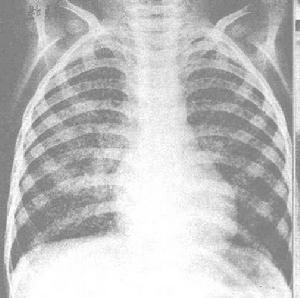

肺莢膜組織胞漿菌病X線圖2.慢性空洞型 主要發生於肺氣腫、肺結核等或肺結構破壞性病變患者,因異常空洞有利於病原菌逃避人體免疫機制的干擾,更好的繁殖。臨床表現與肺結核極為相似,低熱、盜汗、體重下降、咳嗽、咳黏膿痰,逐漸出現呼吸困難。此型除少部分病人自愈,多數進展,最終導致肺纖維化,往往死於呼吸衰竭。

3.進行性播散型 此型少見,發生於免疫抑制患者或老年人、兒童。主要播散至網狀內皮系統,患者全身症狀重,常有高熱、呼吸困難、肝脾腫大、淋巴結腫大、黃疸、貧血,可有口腔及胃腸道潰瘍、心內膜炎、腦膜炎和阿狄森氏病。X 線表現為兩肺部粟粒狀陰影或散在結節狀病變,類似粟粒型肺結核。年幼兒童或AIDS 病人進展較迅速,其他病人進展相對緩慢,死亡率達80%。

其他輔助檢查:X 線表現為結節性浸潤,單個或多個薄壁空洞,周圍有炎症浸潤,病變主要在上葉,可有纖維化,上葉收縮,與肺結核常難鑑別。